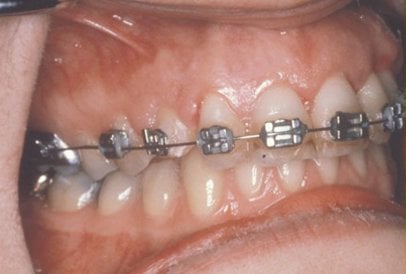

In cases where the eyeteeth will not erupt spontaneously, the orthodontist and oral surgeon will work together to get these teeth to erupt. Each case must be evaluated on an individual basis, but treatment will usually involve a combined effort between the orthodontist and the oral surgeon. The oral surgeon will expose and bracket the impacted eyetooth.

The goal is to erupt the impacted tooth and not to extract it. Once the tooth has moved into its final position, the gum around it will be evaluated. In some circumstances, there may be some minor “gum surgery” required.